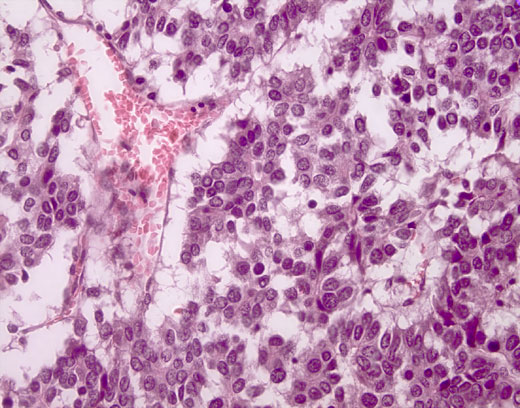

Cross-section #14 - 40X